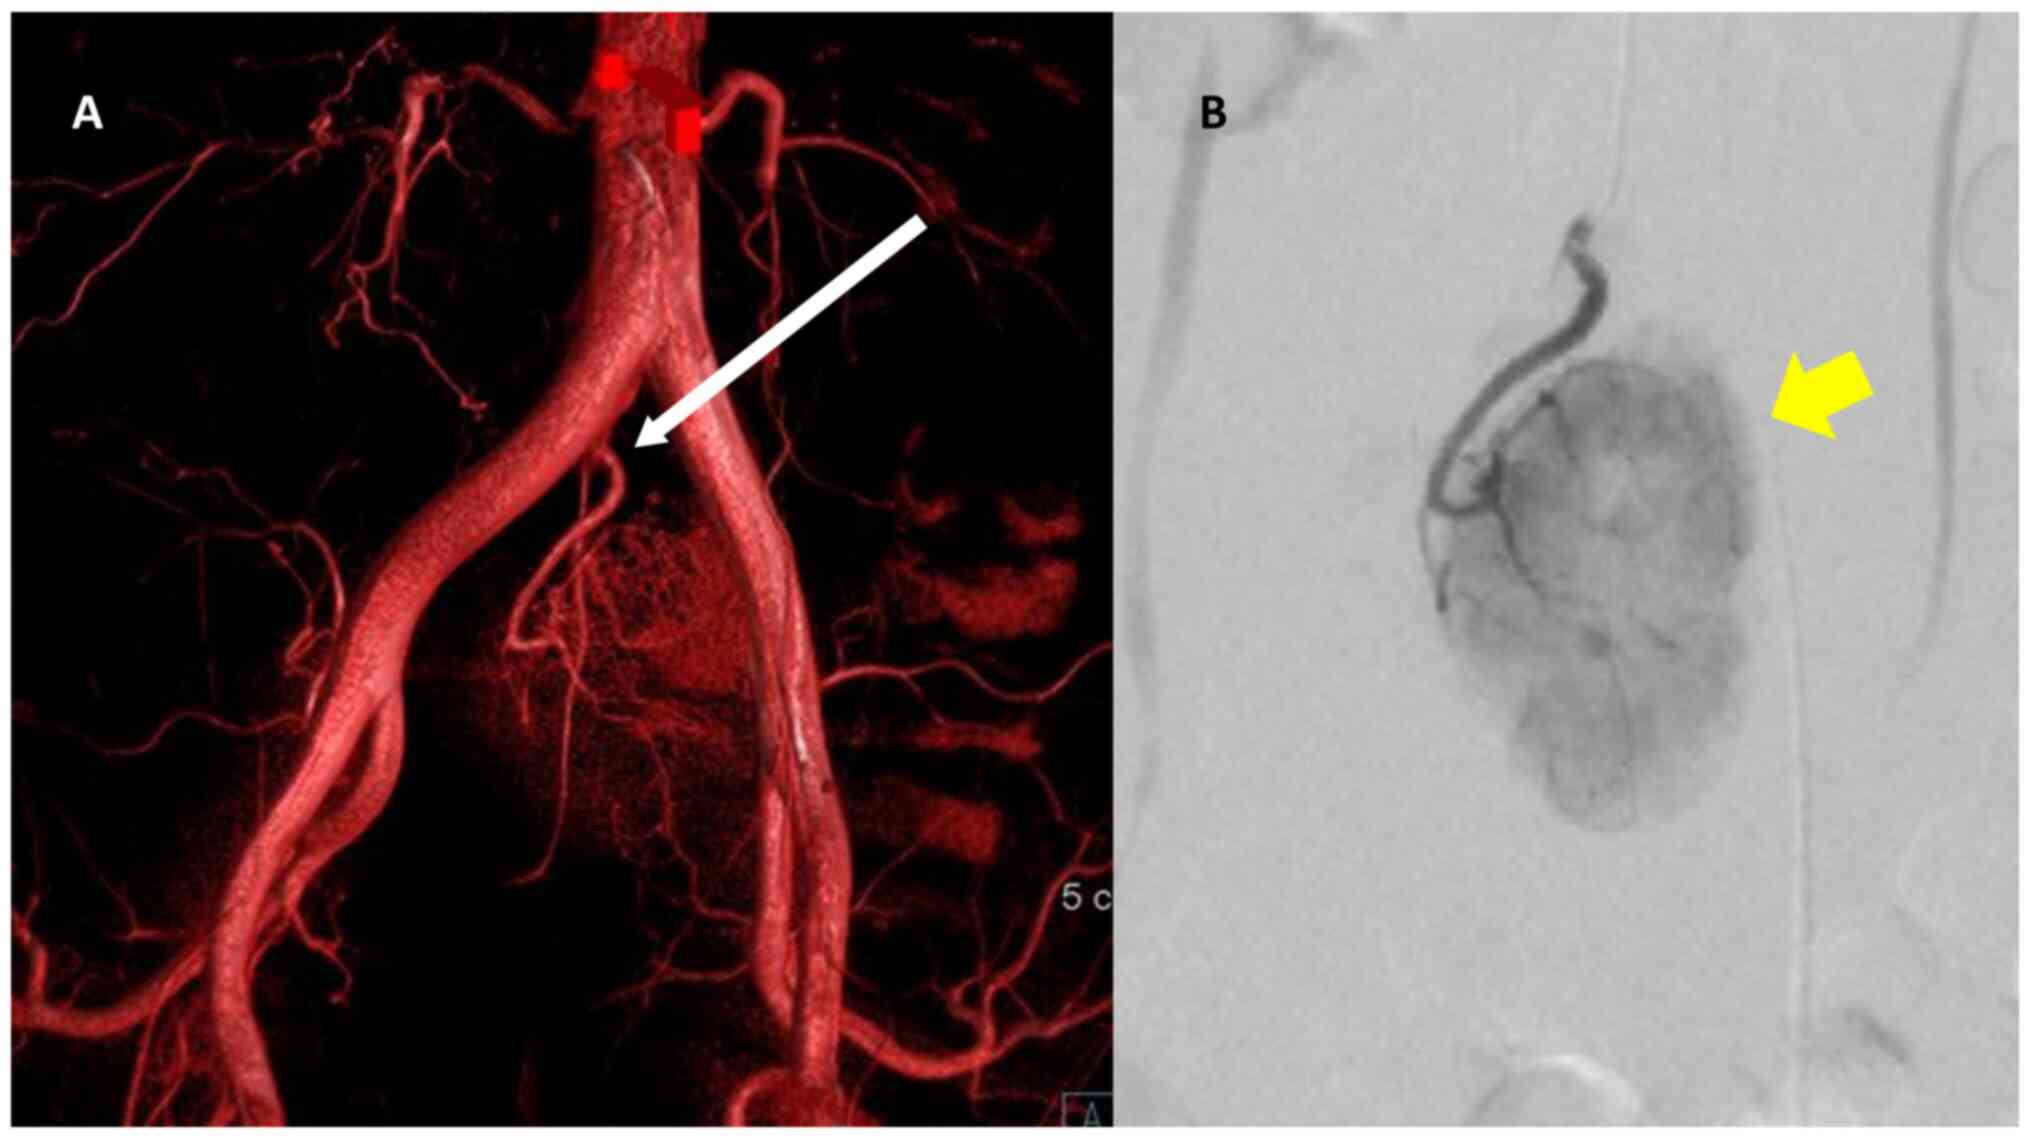

A 44-year-old man presented with a history of diarrhea at another hospital. He was diagnosed with acute enteritis with computed tomography (CT), and the diarrhea was relieved after a few days. The CT scan incidentally revealed a pelvic retroperitoneal mass with calcification, and he was referred to Osaka University Hospital. The patient underwent appendectomy for appendicitis 30 years ago, and had no viral infection or history of any other diseases. The pelvic calcification was previously identified in previous abdominal X-rays, but further examination was not performed. Physical examination revealed no abnormal symptoms. Laboratory blood tests, including for tumor makers (CA19-9 and carcinoembryonic antigen) were normal. Any abnormal finding was not detected by colonoscopy. The abdominal contrast-enhanced CT scan revealed a well-defined 50x30 mm mass behind the sigmoid mesenteric, under the bifurcation of the aorta in the pelvic retroperitoneal. Non-enhanced phase imaging revealed coarse calcification inside the mass, and evident contrast enhancement was observed in the mass during the arterial phase (Fig. 1). Magnetic resonance imaging (MRI) also revealed a well-defined 50x30 mm solid mass situated in the pelvic retroperitoneal. The mass demonstrated heterogeneous and moderately hyperintense signal intensity, and the low signal intensity corresponded to calcification in the T2-weighed images and diffusion-weighted images (Fig. 2). A positive emission tomography/CT scan was performed to exclude the possibility of paraneoplastic manifestations of a primary tumor, and it revealed a 50x30 mm space-occupying lesion with hypermetabolic activity (SUVmax at 4.1) (Fig. 3). Possible differential diagnosis based on the images were CD, primary mesenteric gastrointestinal stromal tumor or leiomyoma. At first, a diagnosis of CD was doubted as the tumor had calcification, exhibited a strong contrast in imaging, had an uniform edge and a relatively uniform inside on the abdominal CT scan; the tumor was generally isointense on T1 weighted images and hyperintense on T2 images (8). Surgical resection following embolization was suggested. Angiographically, the tumor was hypervascular with a dense capillary blush, and it was supplied by the middle sacral artery (Fig. 4). The vasculature of the mass was embolized by DMSO and the patient was operated on the following day.

PET CT scan findings. (A and B) PET CT scan sagittal. (C) PET CT scan axial; the arrow shows the 50x30 mm space-occupying lesion with hypermetabolic activity (SUVmax at 4.1) in the pelvic retroperitoneal. PET CT, positron emission tomography computed tomography.

Angiography findings. (A and B) The yellow arrow shows the mass with a dense capillary blush. The mass was supplied by the middle sacral artery (white arrow).